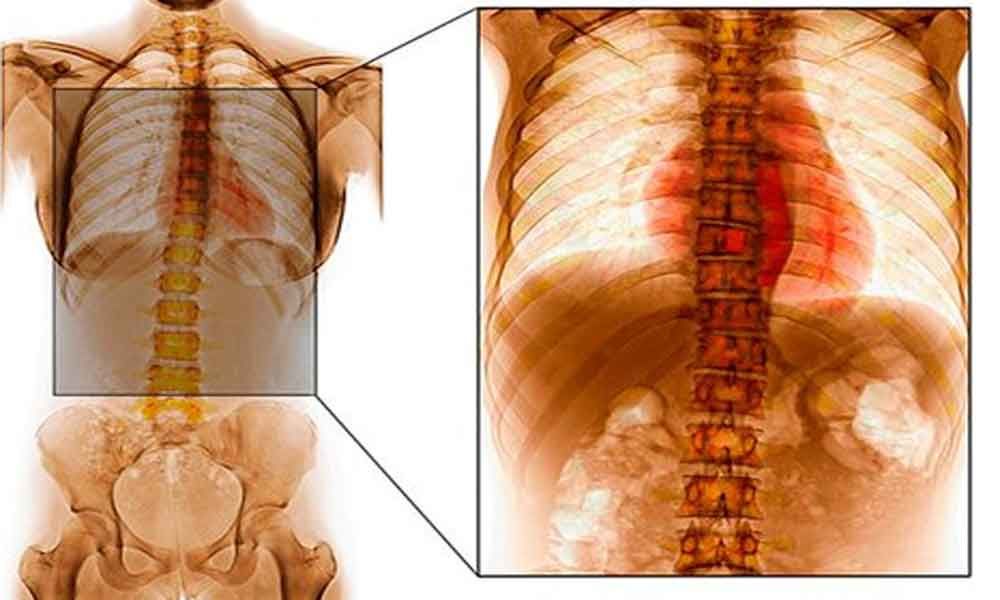

Spinal tuberculosis is a destructive form of tuberculosis. It accounts for approximately half of all cases of musculoskeletal tuberculosis. Spinal tuberculosis is more common in children and young adults. The incidence of spinal tuberculosis is increasing in developed nations. Genetic susceptibility to spinal tuberculosis has recently been demonstrated. Characteristically, there is destruction of the intervertebral disk space and the adjacent vertebral bodies, collapse of the spinal elements, and anterior wedging leading to kyphosis and gibbus formation. The thoracic region of vertebral column is most frequently affected. Formation of a ‘cold’ abscess around the lesion is another characteristic feature.

The incidence of multi-level noncontiguous vertebral tuberculosis occurs more frequently than previously recognized. Common clinical manifestations include constitutional symptoms, back pain, spinal tenderness, paraplegia, and spinal deformities.For the diagnosis of spinal tuberculosis magnetic resonance imaging is more sensitive imaging technique than x-ray and more specific than computed tomography. Magnetic resonance imaging frequently demonstrates involvement of the vertebral bodies on either side of the disk, disk destruction, cold abscess, vertebral collapse, and presence of vertebral column deformities.